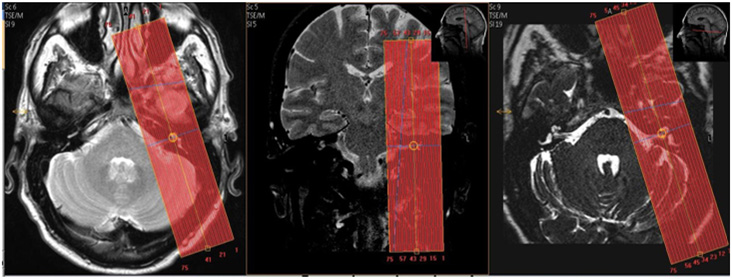

| AXIAL | T2 | 3D TSE | 0.5 | 0 | None | 12 | Small FOV, F-H about 2.8 cm, centered on IACs. |

| COR | T2 | 3D TSE | 0.5 | 0 | None | 12 | Small FOV, cover all of IAC, A-P about 5.8 cm, centered on IACs. |

| R SAG OBLIQ | T2 | 3D TSE | 0.5 | 0 | None | 12 | Perpendicular to R IAC. Cover from lateral margin of medulla to lateral margin of semicircular canals, about 4.0 cm. |